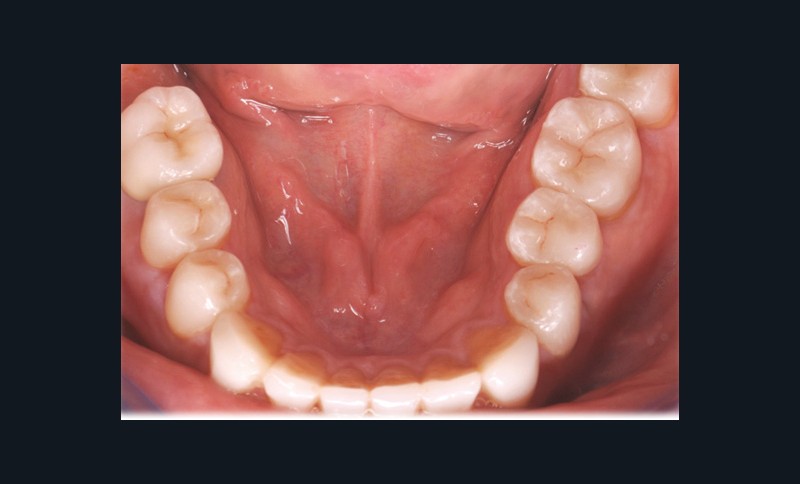

Leurs indications cliniques sont particulièrement fréquentes dans les contextes d’usure érosive pour lesquels il est souvent nécessaire d’augmenter la dimension verticale d’occlusion (DVO) afin d’ouvrir l’espace anatomique antérieur (fig. 5 et 6). Leur dénomination, qui dépend de leur niveau de recouvrement, varie du table top (fig. 7) au veneerlay (recouvrement des faces occlusale et vestibulaire sur de faibles épaisseurs et en intra-amélaire) (fig. 8 et 9). Mais leur indication est aussi posée sur les dents fissurées (« craked tooth syndrome »), dans les cas de dents présentant une fragilisation cuspidienne ou encore en présence d’une dent postérieure en infraposition occlusale.